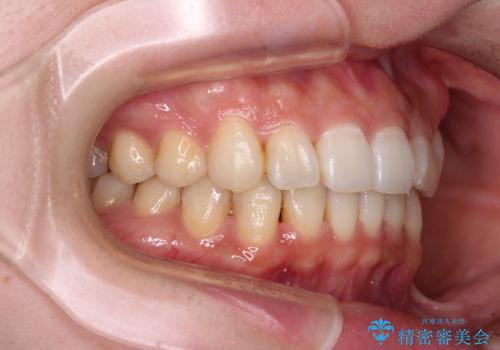

- 前歯のデコボコと深い咬み込みを気にして来院された患者様です。

インビザラインを用いて、前歯の叢生を解消するとともに、深い咬み合わせ(ディープバイト)を改善していくこととしました。

奥歯を後方に直立させることで深い咬み合わせを改善を図り、隠れていた下顎前歯が見えるほどになりました。